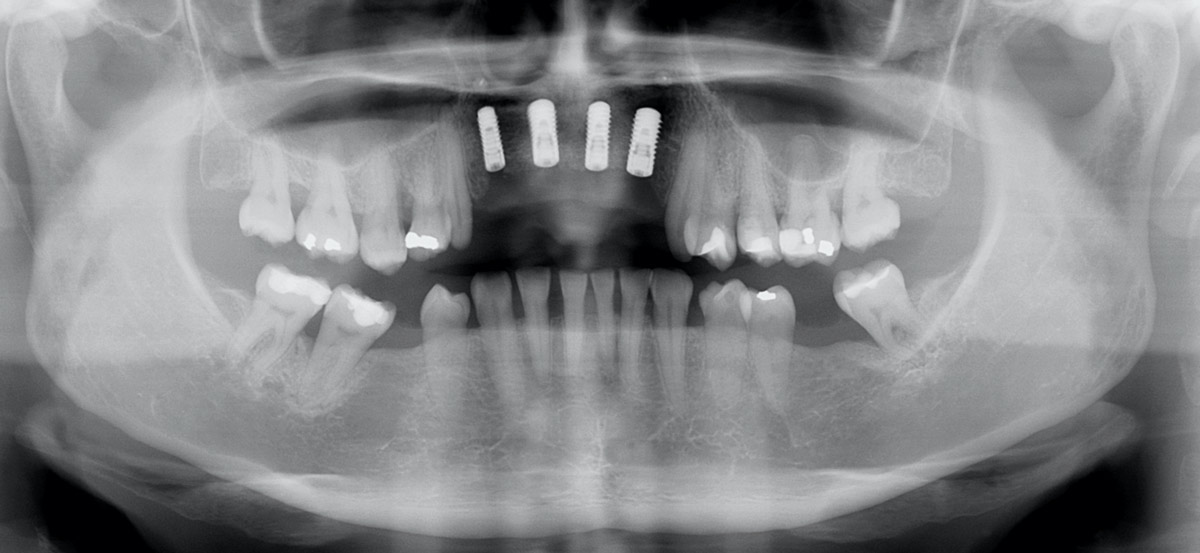

13/17 - X-ray scan after implant insertionRestoration of all four incisors with maxgraft® bonebuilder - Dr. Dr. Dr. O. Blume